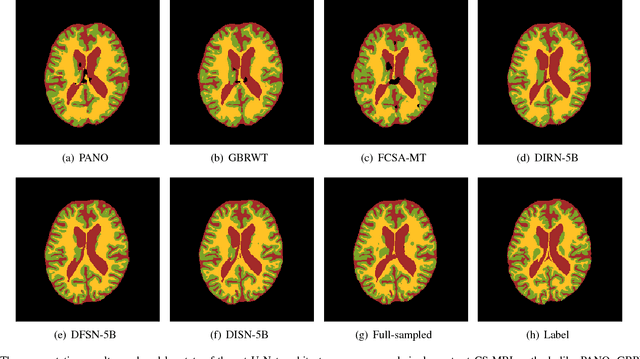

Abstract:The need for fast acquisition and automatic analysis of MRI data is growing in the age of big data. Although compressed sensing magnetic resonance imaging (CS-MRI) has been studied to accelerate MRI by reducing k-space measurements, in current CS-MRI techniques MRI applications such as segmentation are overlooked when doing image reconstruction. In this paper, we test the utility of CS-MRI methods in automatic segmentation models and propose a unified deep neural network architecture called SegNetMRI which we apply to the combined CS-MRI reconstruction and segmentation problem. SegNetMRI is built upon a MRI reconstruction network with multiple cascaded blocks each containing an encoder-decoder unit and a data fidelity unit, and MRI segmentation networks having the same encoder-decoder structure. The two subnetworks are pre-trained and fine-tuned with shared reconstruction encoders. The outputs are merged into the final segmentation. Our experiments show that SegNetMRI can improve both the reconstruction and segmentation performance when using compressive measurements.

Abstract:Compressed sensing MRI is a classic inverse problem in the field of computational imaging, accelerating the MR imaging by measuring less k-space data. The deep neural network models provide the stronger representation ability and faster reconstruction compared with "shallow" optimization-based methods. However, in the existing deep-based CS-MRI models, the high-level semantic supervision information from massive segmentation-labels in MRI dataset is overlooked. In this paper, we proposed a segmentation-aware deep fusion network called SADFN for compressed sensing MRI. The multilayer feature aggregation (MLFA) method is introduced here to fuse all the features from different layers in the segmentation network. Then, the aggregated feature maps containing semantic information are provided to each layer in the reconstruction network with a feature fusion strategy. This guarantees the reconstruction network is aware of the different regions in the image it reconstructs, simplifying the function mapping. We prove the utility of the cross-layer and cross-task information fusion strategy by comparative study. Extensive experiments on brain segmentation benchmark MRBrainS validated that the proposed SADFN model achieves state-of-the-art accuracy in compressed sensing MRI. This paper provides a novel approach to guide the low-level visual task using the information from mid- or high-level task.